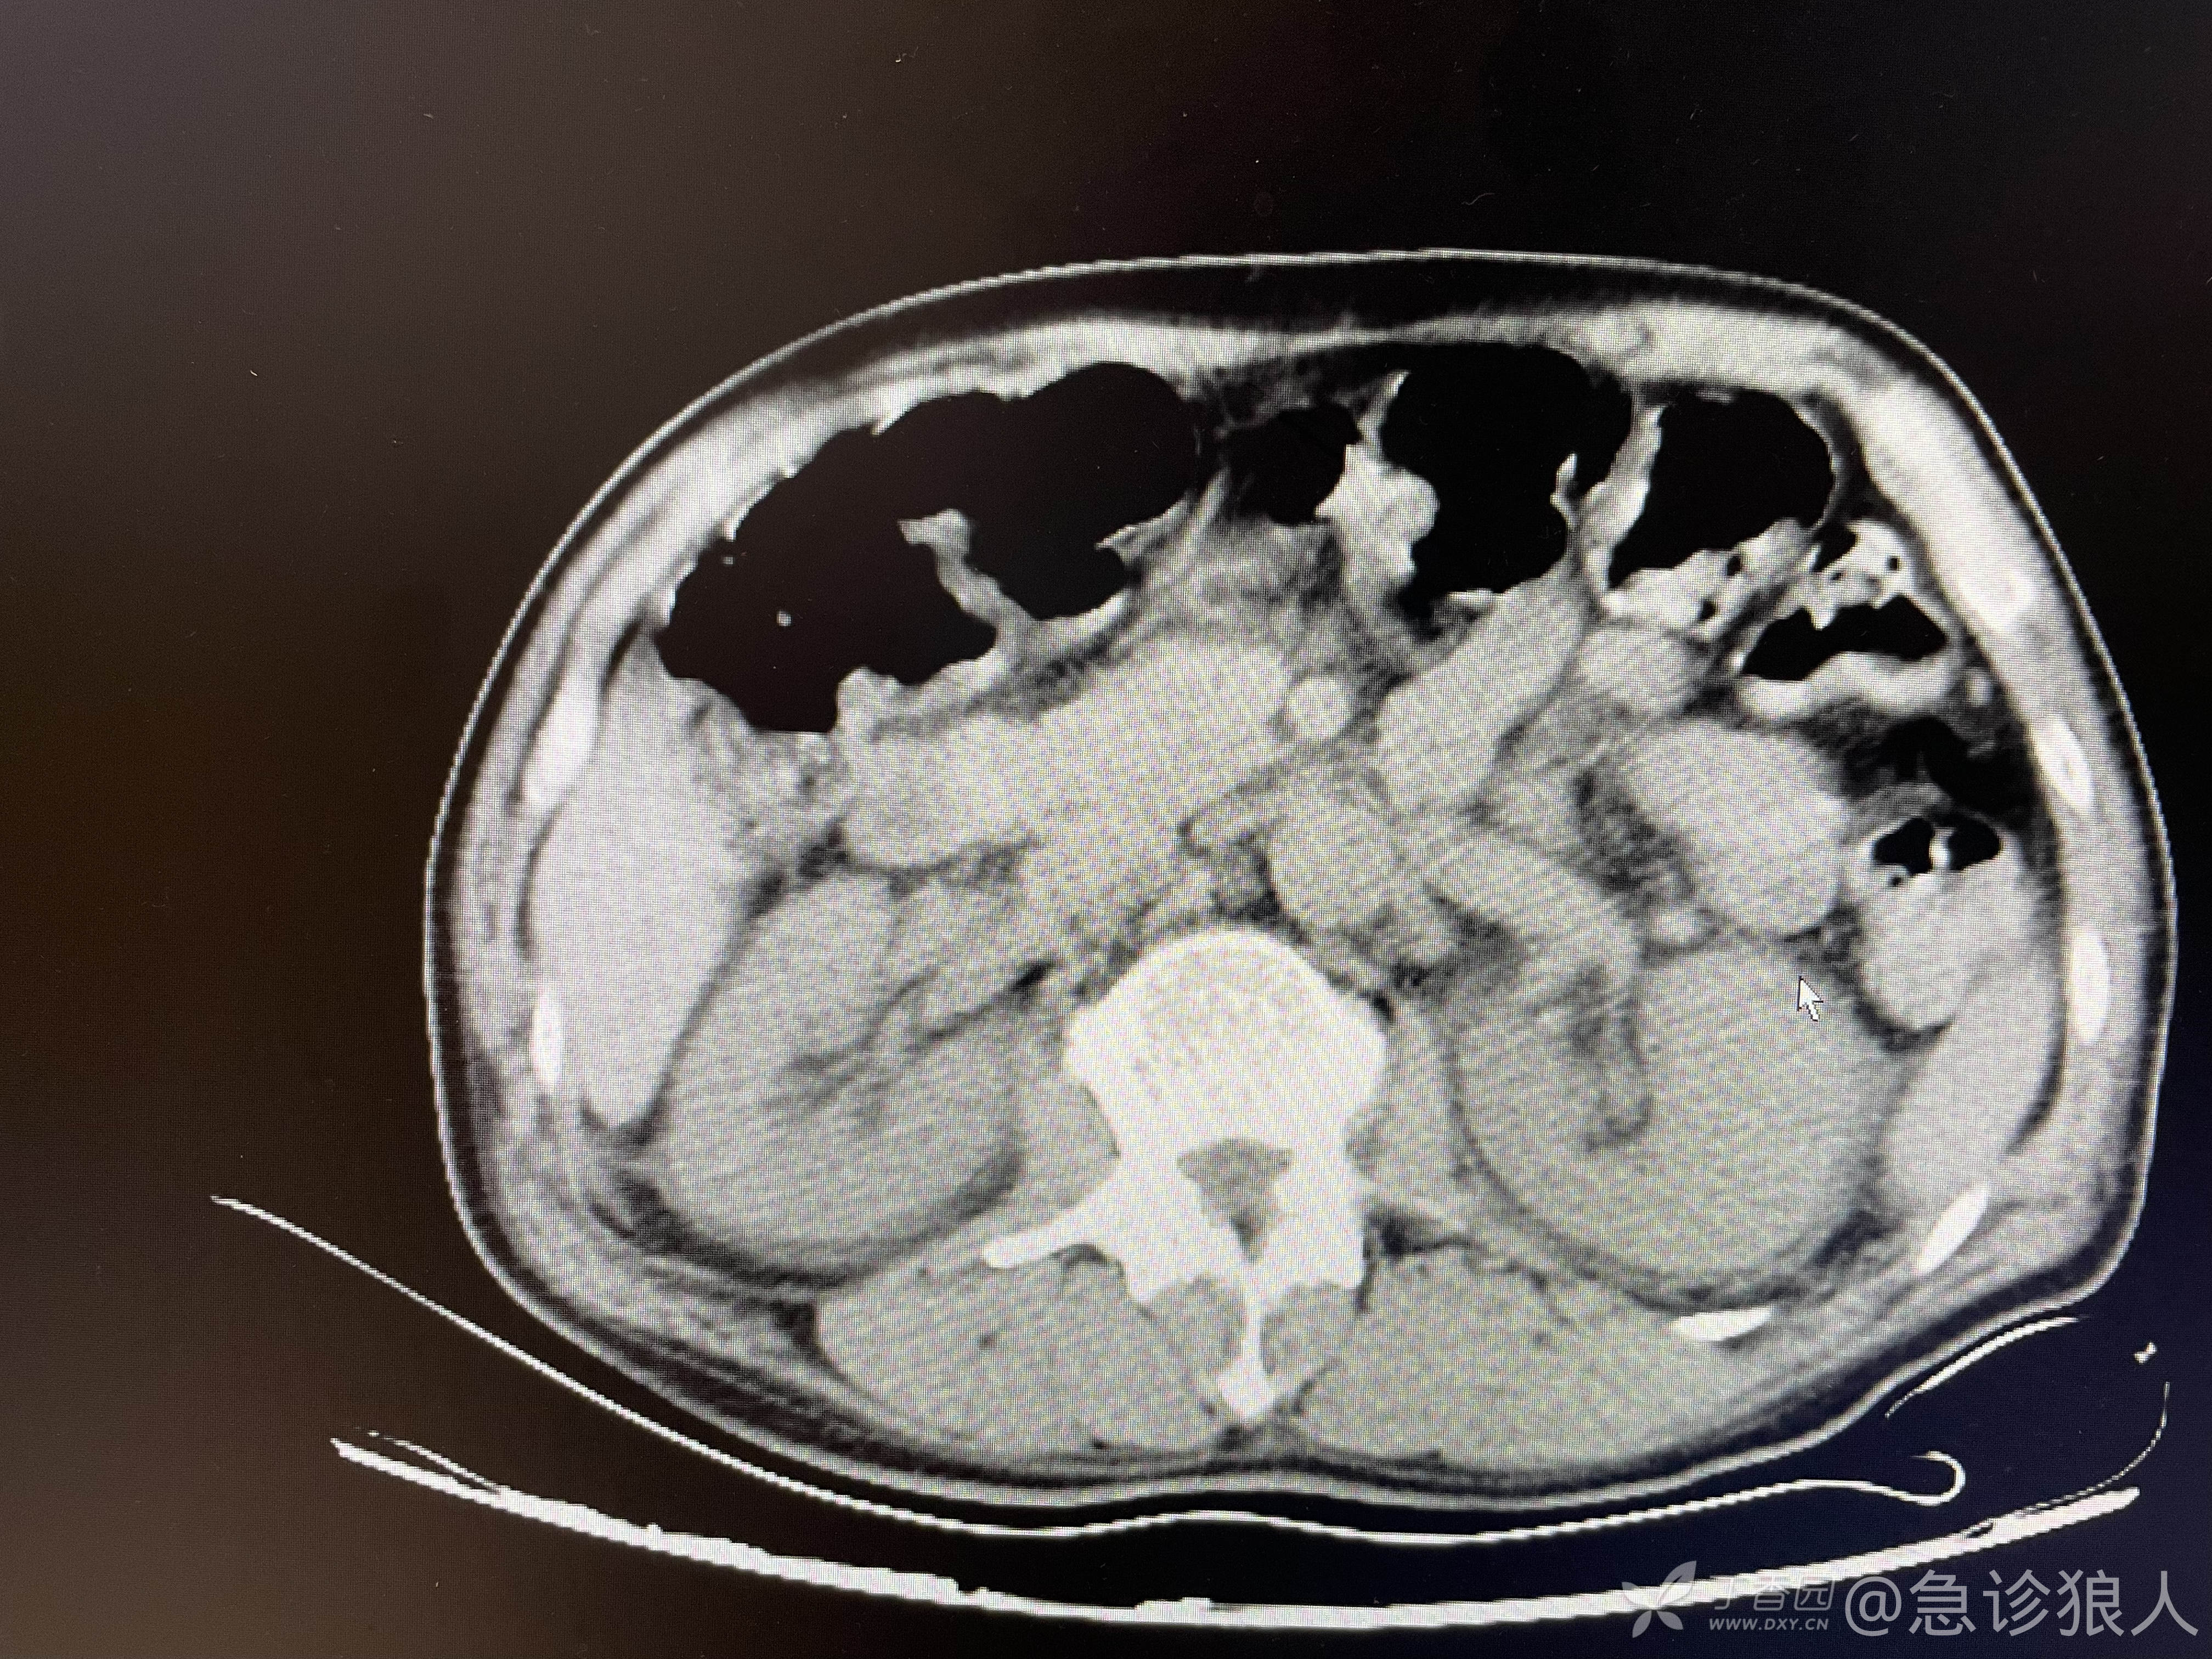

可是ct如下:

看完ct,什么感觉?

脑内软化灶,有点时间了,肾周渗出,可能是新的!

立即把病人转入抢救室,完善血气,血气低钾、低钙,其他正常!